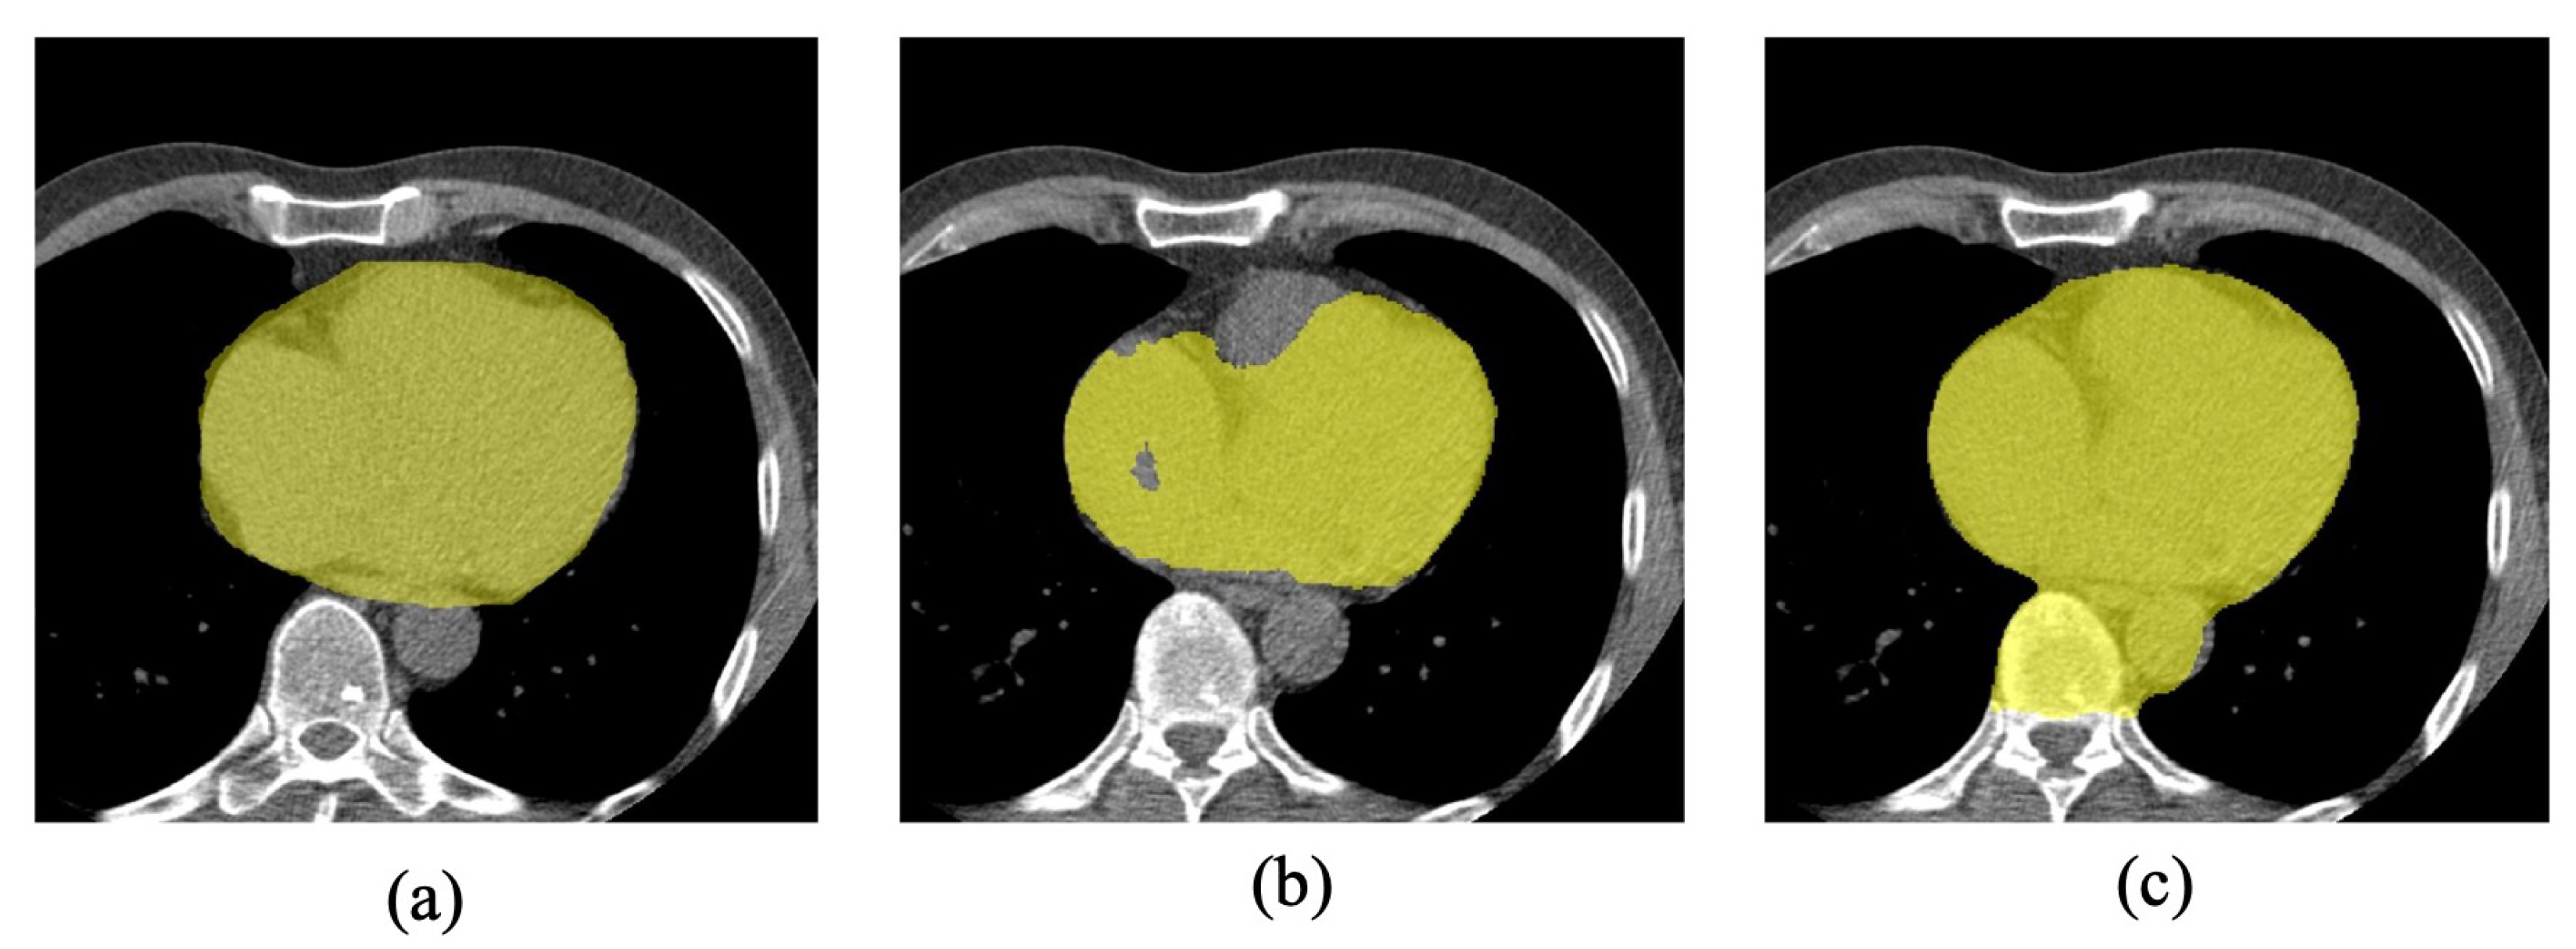

To visualize the prediction of 3D attention U-Net, we show the region inside pericardium segmentation results of 3D attention U-Net with and without deep supervision in Figure 9. Without deep supervision, the segmentation focused too much on the inside region and misses some pixels around the pericardium. This reduced the performance of EAT segmentation sharply, as most EAT locates near the pericardium.

Figure 9.

Segmentation results of 3D attention U-Net. (a) ground truth. (b) segmentation results of 3D attention U-Net without deep supervision. (c) segmentation results of 3D attention U-Net with deep supervision.